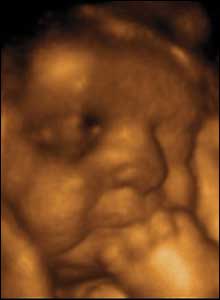

34 weeks gestation. 34cm from crown to rump.

8 of 10

While newborns do not smile until 4-6 weeks after birth, babies in the uterus do. Maybe because the uterus is warm, comfortable, and shielded from loud noise and bright light.